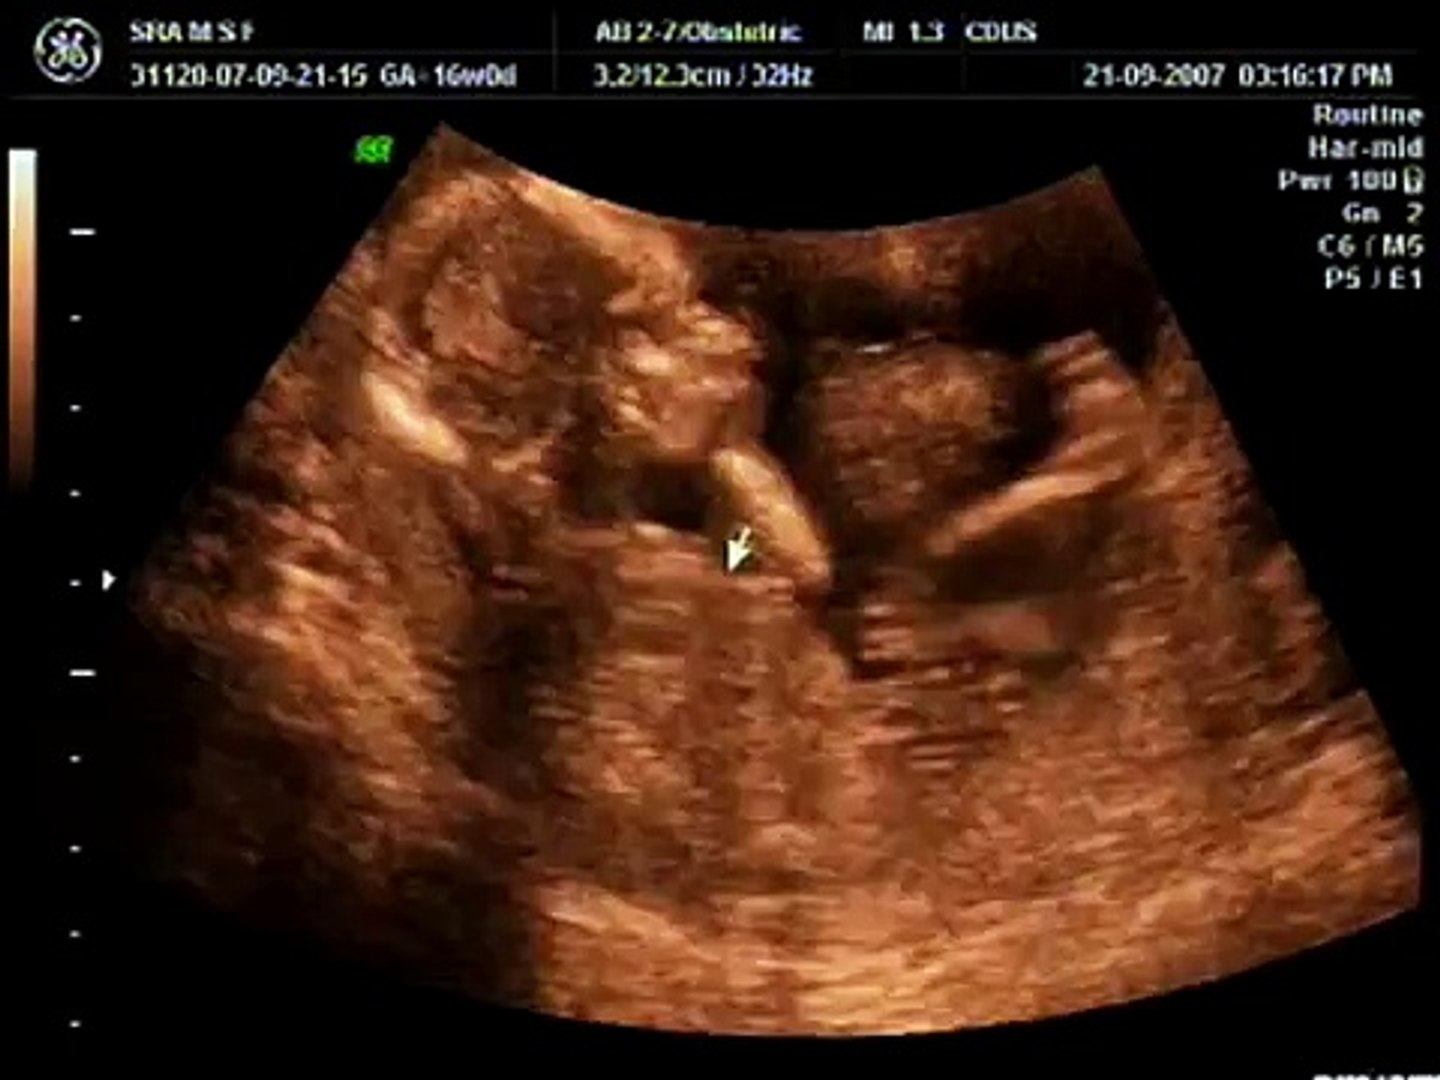

Ecografia 3d 3 meses. Una de las claves para obtener una buena imagen del feto en 3D es obtener previamente una imagen de alta calidad en 2D. Distintos tipos de ecografías durante el embarazo. A ecografia em três ou inclusivo em quatro dimensões é em linhas gerais a ecografia tradicional em duas dimensões tomada com um número suficiente de imagens desde vários planos distintos da mesma estrutura.

Estas imágenes permiten que puedas ver a tu bebé en tres dimensiones en lugar de dos. Ecografia obstétrica 2D 3D 4D. Gestação de 3 Meses.

Para que serve a ecografia tridimensional ou 3D4D. Em que contribui para o diagnóstico durante a gravidez. Assim realizando um tratamento posterior destas imagens obtém-se a ecografia em três dimensões.

Te damos todos los detalles para saber qué puedes esperar de cada tipo de ecografía en cada momento. El Dr García hace una explicación sobre el vídeo. Assim realizando um tratamento posterior destas imagens obtém-se a ecografia em três dimensões. A ecografia 3D4D permite-nos avaliar o feto nos três planos ortogonais do espaço. Encontrará nos nossos centros promoções especiais para que desfrute de uma sessão plena de emoção. Ola mamas queria saber se alguem da zona de penafiel ja fez alguma eco morfologica a 3d com p1 tenho que fazer pro mes que vem e gostava de dar uma espreitadela ao meu dinis pk estou na duvida se na clinica arrifana. O que se vê porque é necessária o que é o embrião e como se pode observar. Primeira ecografia entre a 9ª e a 12ª semana segunda ecografia entre a 19ª e a 22ª semana e terceira ecografia entre a 29ª e 32ª semana. Es decir una técnica de imagen no invasiva que nos permite observar dentro del cuerpo de una persona.

Paguei 120 fiz a eco em 2D e em 3D gravaram me a ecografia e trouxe umas fotos em A4 senao me engano foram 4 eu estava com 23 semanas senão me engano olha adorei. En una imagen 3D puedes ver profundidad y forma dando una claridad no tan evidente en una ecografía 2D. Isso acontece porque o período mais crítico da gestação já passou. Essas imagens obtêm uma qualidade quase fotográfica. Growing up in vermont in the country nothing said spring to me like asparagus and morel mushrooms. Ecografia das 12 semanas. Além do feto permite a visualização da placenta líquido amniótico cordão umbilical e estruturas pélvicas.